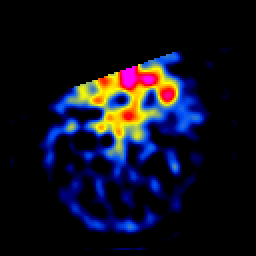

SPECT TL Study #4 -- Slice #13

[Home][Help][Clinical][Tour 1][Tour 2][Tour 3] Slice 13